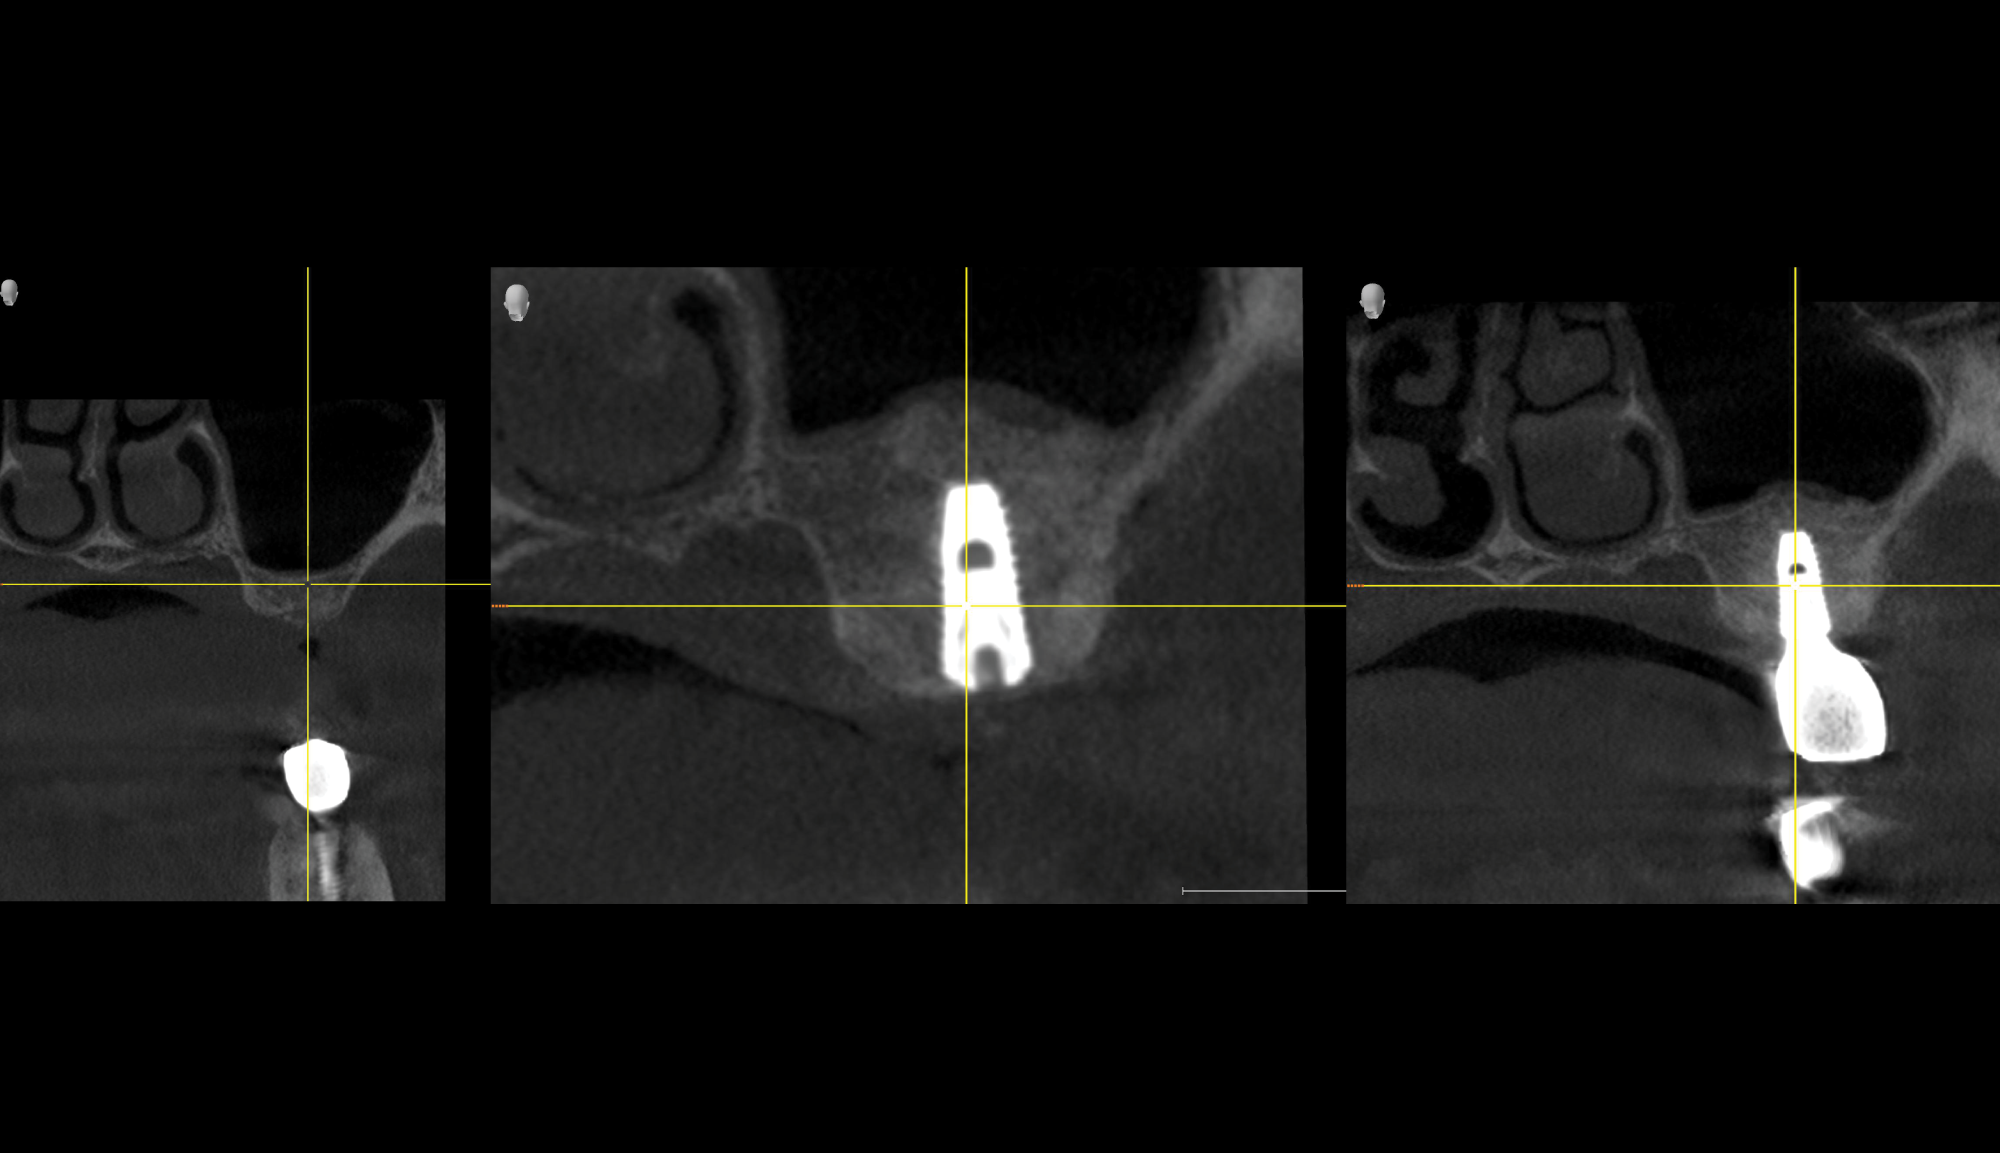

Director’s Clinical Cases

Director’s Clinical Cases